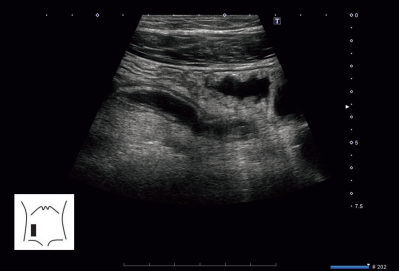

血液所見:赤血球 430 万、Hb 12.6 g/dL、Ht 40 %、白血球 13,500、血小板 25 万。血液生化学所見:総蛋白6.8 g/dL、アルブミン 4.0 g/dL、AST 20 U/L、ALT 10 U/L、尿素窒素 12 mg/dL、クレアチニン 0.5 mg/dL、Na 140 mEq/L、K 4.0 mEq/L、Cl 102 mEq/L。CRP 8.2 mg/dL。腹部超音波像を別に示す。